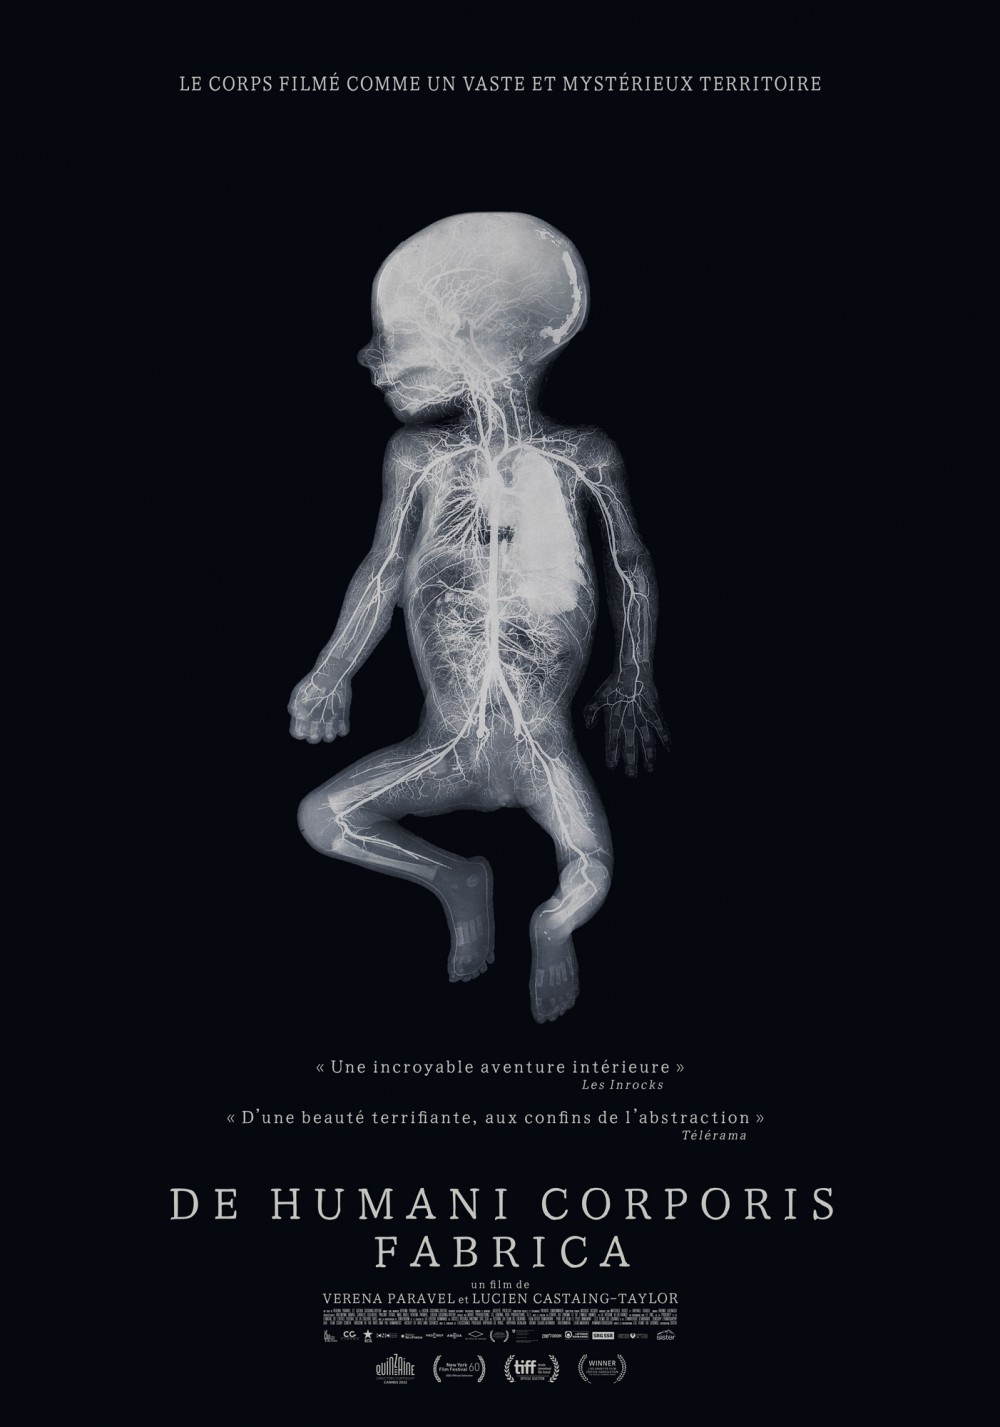

Reprenant le titre d’un traité d’anatomie du XVIe siècle, «De Humani Corporis Fabrica» s’intéresse à ce qui se passe non pas à l’intérieur de l’hôpital mais à l’intérieur des patients. Aux liens qui unissent le corps médical aux corps défaillants, fracassés, au bord de l’extinction. Il y a cinq siècles l’anatomiste André Vésale ouvrait pour la première fois le corps au regard de la science. «De Humani Corporis Fabrica» ouvre aujourd’hui le corps au cinéma. On y découvre que la chair humaine est un paysage inouï qui n'existe que grâce aux regards et aux attentions des autres. Les hôpitaux, lieux de soin et de souffrance, sont des laboratoires qui relient tous les corps du monde…